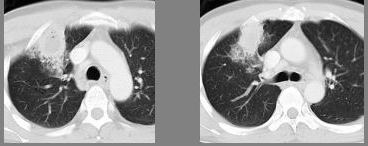

75、单项选择题

HIV阳性患者近来咳嗽,胸闷,胸片检查发现病变,CT检查如图,最可能的诊断为()

A.肺淋巴瘤

B.卡波济肉瘤

C.双肺感染

D.间质性肺炎

E.肺癌

点击查看答案